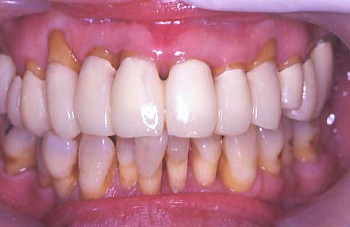

⑮ 上下全歯牙の歯周外科処置終了、二か月が経過

治療前と治療後の口腔内を比較

初診時の口腔内の状態

最終治療後の状態